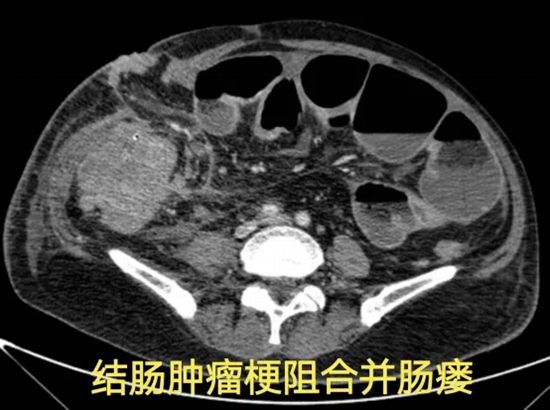

病例一:肠梗阻、重度感染、晚期肿瘤……在绝境中寻找生机

病情简述:60岁男性,结肠癌肝肺转移,经历多线治疗后并发肠梗阻、肠造口术后出现严重腹腔感染、重度营养不良。

诊疗破局:面对肿瘤压迫、感染、营养不良三重打击,团队未轻言放弃。从精细化的伤口缝合入手,先为患者创造手术条件;最终通过多学科协作,一次性完成“肿瘤切除+感染清理+腹壁重建”的高难度手术。

技术体现:在极端复杂的晚期肿瘤并发症面前,系统的整合救治能力是逆转危局的关键。